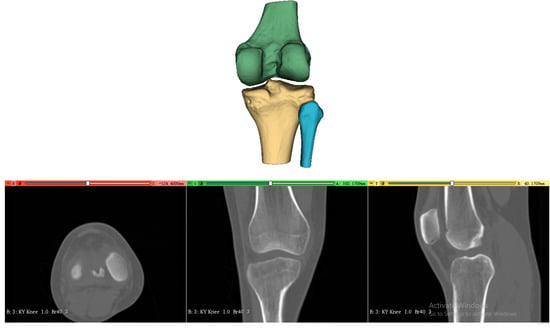

2.2. 3D Femoral Model Processing

The processing of the three-dimensional femoral model consists of two essential steps, reconstruction of the distal femoral surface model and establishment of the initial sagittal plane. Starting with high-resolution CT data of the patient’s knee (slice thickness 1 mm, pixel spacing 0.5 mm), the system first reconstructs the three-dimensional surface model of the distal femur, as shown in Figure 2. This reconstruction process utilizes threshold-based segmentation that takes advantage of the natural contrast between bone and surrounding tissues in CT images, followed by morphological operations to refine the initial segmentation. The resulting volumetric data are then converted into a surface mesh model through a marching cubes algorithm, producing a detailed representation of the distal femoral surface.

Figure 2. Three-dimensional surface model reconstruction of the distal femur from CT images.